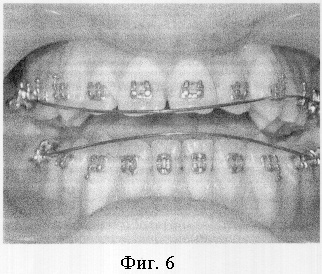

Пример 1. Пациент Б.С., 17 лет. Диагноз: дистопия верхних и нижних клыков (фиг.4). Проводилось ортодонтическое лечение с использованием брекет-системы. Клыки установлены в зубной ряд, но при этом получена значительная протрузия передних зубов и значительная вертикальная межрезцовая щель (фиг.5).

Под местной анестезией проведена остеотомия во всю толщу альвеолярных частей обеих челюстей над корнями передних зубов. Установлены стальные дуги 0,17×0,25 (паз брекета – 0,18) с реверсионными изгибами. Спустя неделю начаты активации реверсионных изгибов на дугах (фиг.6). Через 2,5 месяца после операции достигнут ортогнатический прикус (фиг.7).